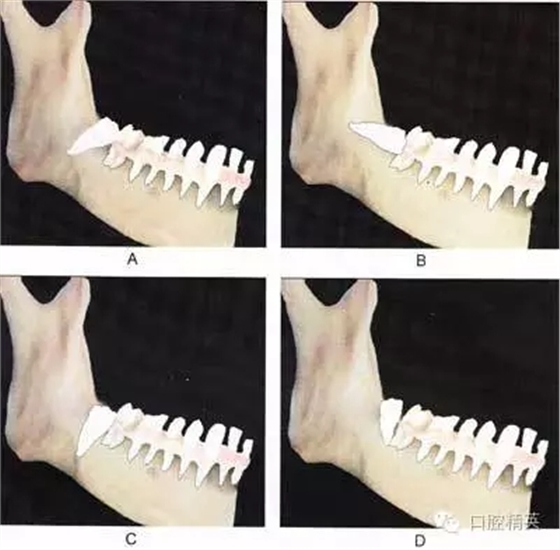

圖⒍1 根據(jù)第三磨牙牙體長軸與第二磨牙牙體長軸所成的角度不同可分為:近中 阻生(圖A):第三磨牙牙冠向近中傾斜;水平阻生(圖B):第三磨牙與第二磨牙牙體長軸相互垂直;垂直阻生(圖C):第三磨牙牙體長軸與第二磨牙平行;遠(yuǎn) 中阻生(圖D):第三磨牙牙冠向遠(yuǎn)中傾斜

A

B

C